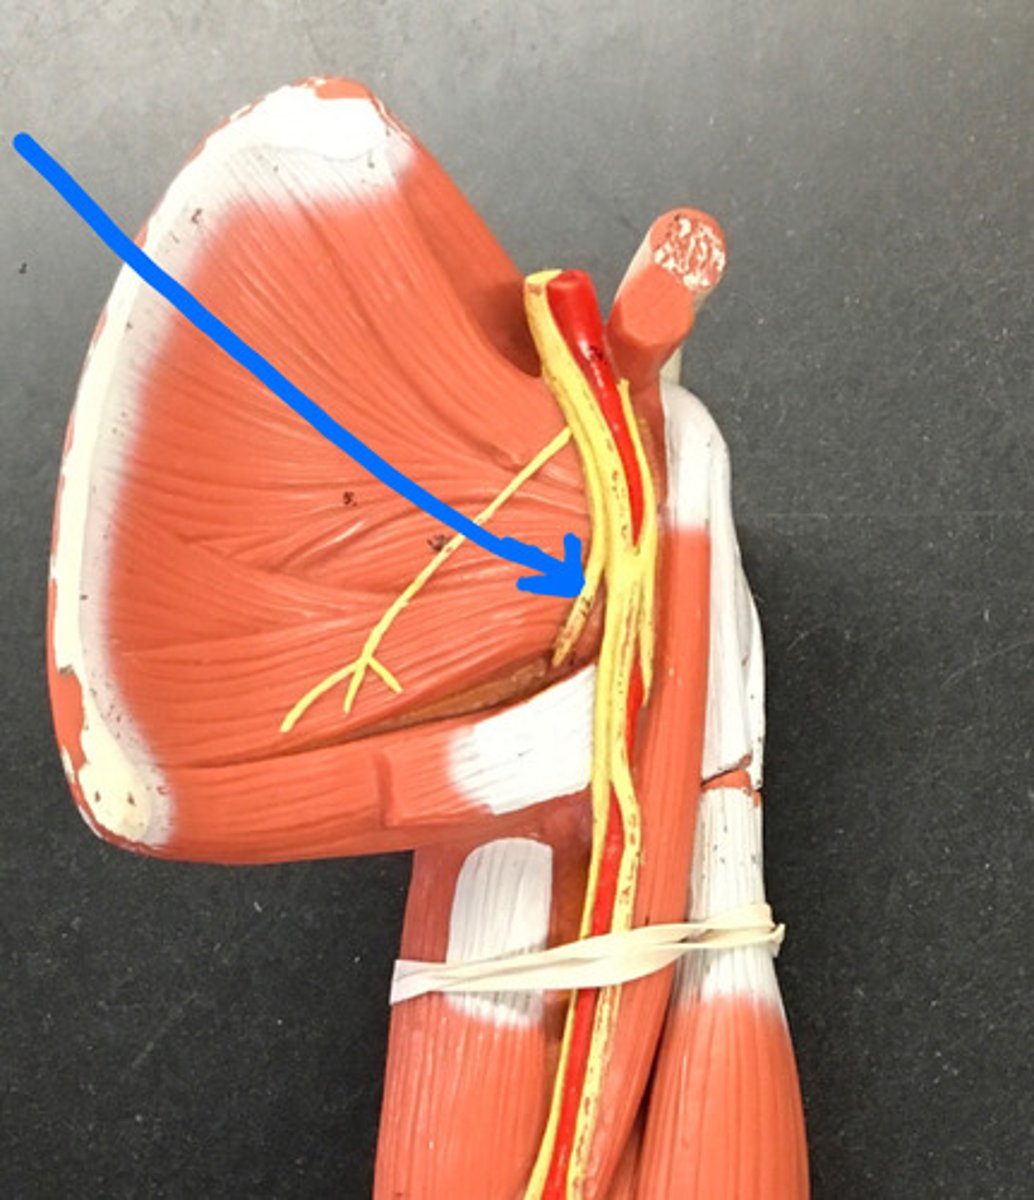

axillary nerve

dives deep near teres major

radial nerve

suprascapular nerve

Branches off the superior trunk

Seen on cadavers or picture

Subscapular nerve